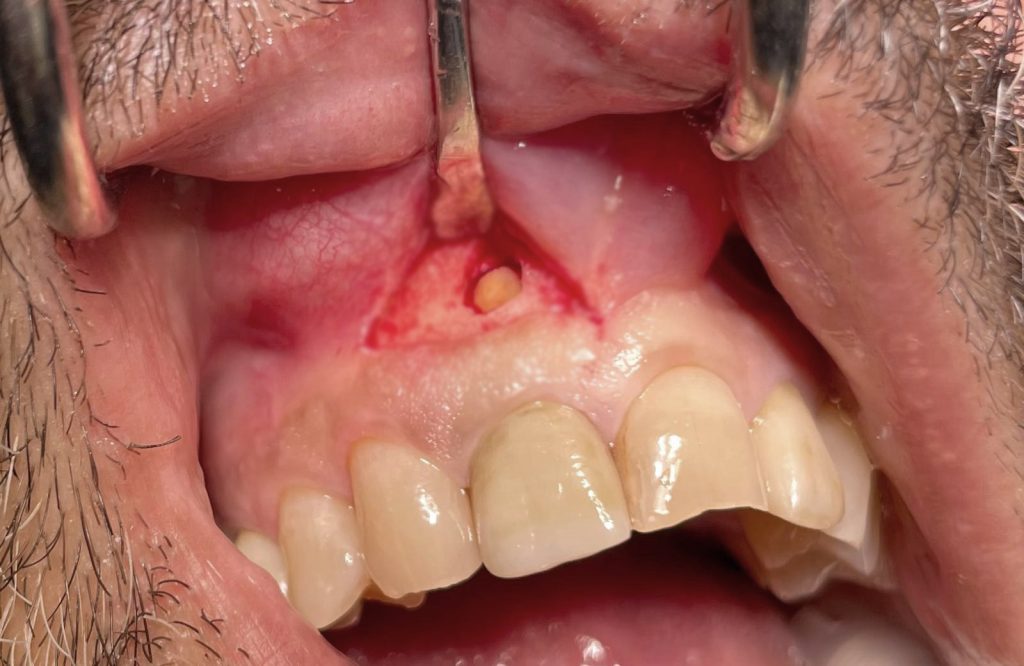

Oggi vi presento un caso di apicectomia dell’elemento 11 eseguito su un paziente che presentava una lesione periapicale.

Abbiamo trattato la lesione effettuando un’amputazione dell’apice radicolare, un’otturazione retrograda dell’apice e una sutura a conclusione dell’intervento.